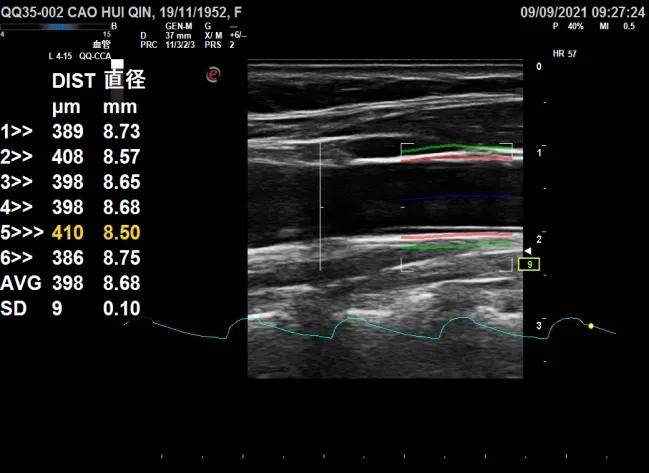

9月13日 , 西安市中医医院功能科作为分中心加入“基于超声射频信号颈动脉内中膜厚度及弹性正常值全国多中心研究项目” 。 该项目由空军军医大学唐都医院超声医学科牵头 , 全国多家三级甲等医院共同合作 , 西安市中医医院成功加入这一多中心研究项目并成为研究的分中心之一 , 标志着医院临床技术和科研水平的进一步提升 , 医疗工作与科研创新相互融合卓有成效 。

研究目的:与全国多家大型三甲医院合作 , 采用超声测量的方法 , 首次开展我国健康人群颈动脉内中膜厚度(IMT)及血管弹性参数的大规模流行病学调查 。 由此制订中国各年龄段人群IMT及血管弹性指标的正常参考值 , 为我国心血管疾病的风险预测和预后评估提供依据 。

研究背景:IMT反映了颈动脉壁的厚度 , 是评估动脉硬化程度的重要参数 。 颈动脉IMT升高是动脉粥样斑块形成早期阶段的典型特征 , 其数值越高 , 则动脉粥样硬化程度越重 , 心梗、脑梗、冠心病等一系列严重心血管疾病死亡风险越高 。 即使在尚未表现出相关心血管症状的人群中 , 也可以发现相当数量的患者已经出现了血管内膜厚度与弹性的改变 。 超声能够无创、快速、准确的测量颈动脉的IMT数值 , 有助于心血管疾病的早期诊断和干预 。 然而 , 我国目前参照的评估标准源于西方的研究 , 这些标准的构建主要源于西方人群的数据 , 目前还没有特异性针对中国人群的评估标准 。 在我国人群中 , 直接套用西方标准将严重影响这一重要参数评估心血管事件风险的准确性 。

受试者获益:本项目开展期限为1个月 。 研究期间拟招募符合要求的志愿者120名 , 年龄为18-80岁 。 我们将为参加调查的志愿者免费进行颈部动脉的超声检查和评估 。 与常规的颈动脉血管超声检查一样 , 颈动脉血管弹性超声检查安全、无创、无辐射,无检查相关风险与不适 。 与常规超声检查不同的是 , 这项检查能够帮助志愿者了解自身颈动脉血管弹性的多模态弹性参数 , 更全面的了解自身血管的健康状况 , 有利于动脉硬化性疾病的风险评估和相关疾病的早期检出 , 做到早发现、早预防、早治疗 。